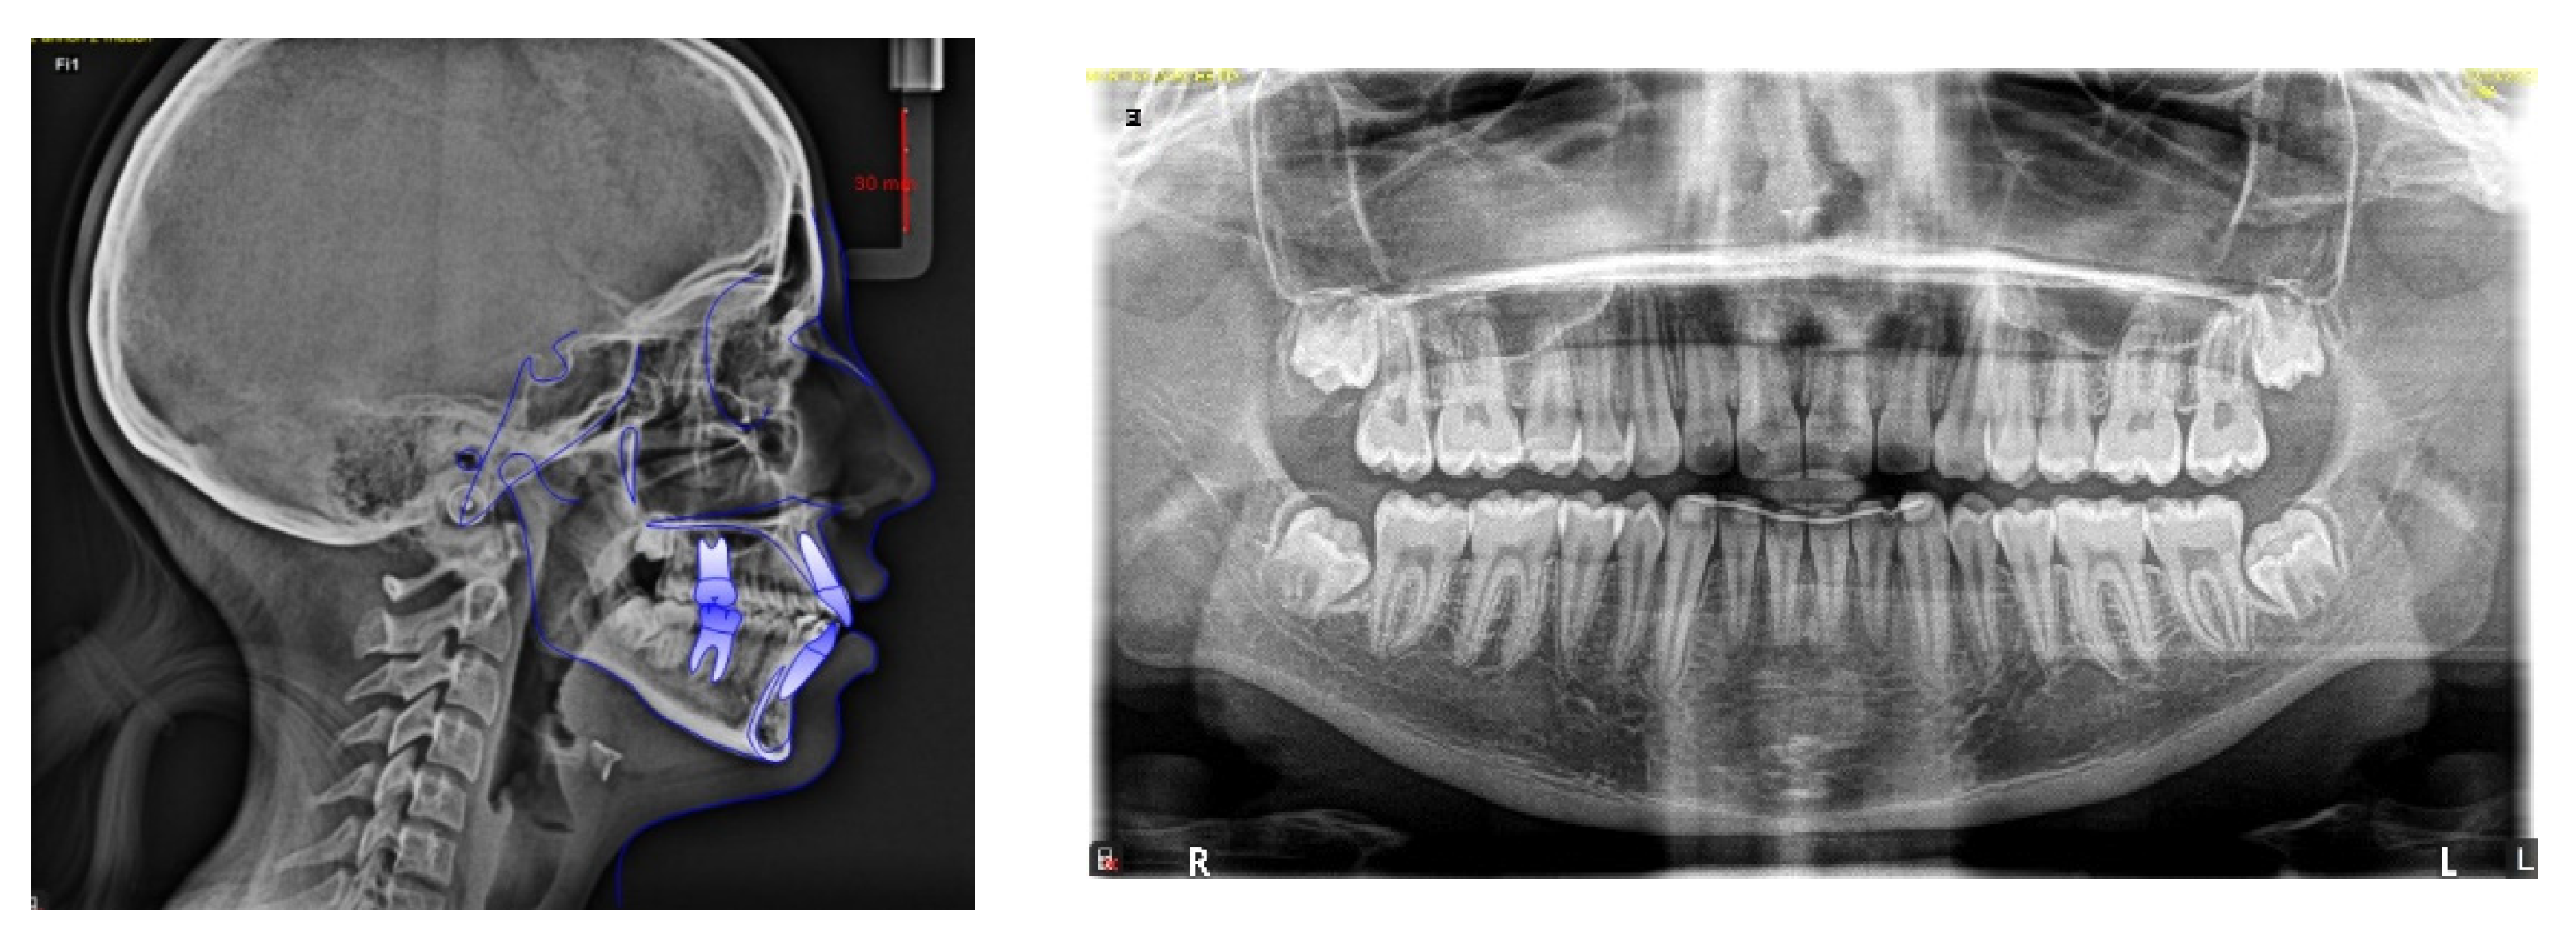

4. Case Report

4.1. Etiology and Diagnosis

4.2. Treatment Objectives

4.3. Treatment Strategy

4.4. Treatment Progress

| Measurements | Norm | Pre-Treatment | Post-Treatment |

|---|---|---|---|

| Anterior Cranial Base(S-N) | 74.5 ± 3 | 66 | 66.5 |

| Facial Axis (BaN-PTGn) | 90° ± 3 | 84.4° | 85.8° |

| Mandibular Lenght (Goc-Me) | 74.5 ± 5 | 61.9 | 64 |

| Posterior Cranial Base (S-Ar) | 34 ± 3 | 30.9 | 31.4 |

| Height Mandibular Ramus (Ar-Goc) | 47.5 ± 5 | 33.9 | 38.3 |

| Saddle angle: (N-S-Ar) | 123° ± 5 | 120.4° | 118.8° |

| Articular angle (S-Ar-Goc) | 143° ± 7 | 150.1° | 149.6° |

| Gonial angle (Ar-Goc-Me) | 130° ± 7 | 128.6° | 129.1° |

| Upper gonial angle (Ar-Goc-N) | 52° ± 3 | 53° | 52.4° |

| Lower gonial angle (Me-Goc-N) | 70° ± 2 | 75.6° | 76.7° |

| Anterior facial height (N-Me) | 113 ± 7 | 105.2 | 108.9 |

| Posterior facial height (S-Goc) | 77.5 ± 7.5 | 62.6 | 67.3 |

| Jarabak Facial Proportion % | 61% ± 3 | 59.5% | 61.8% |

| SNA | 82° ± 2 | 80.9° | 79.7° |

| SNB | 80° ± 2 | 75.1° | 76° |

| ANB | 2° ± 2 | 5.8° | 3.7° |

| U1—palatal plane | 110° ± 2 | 112.7° | 111.2° |

| IMPA | 90° ± 3 | 96.9° | 97.8° |